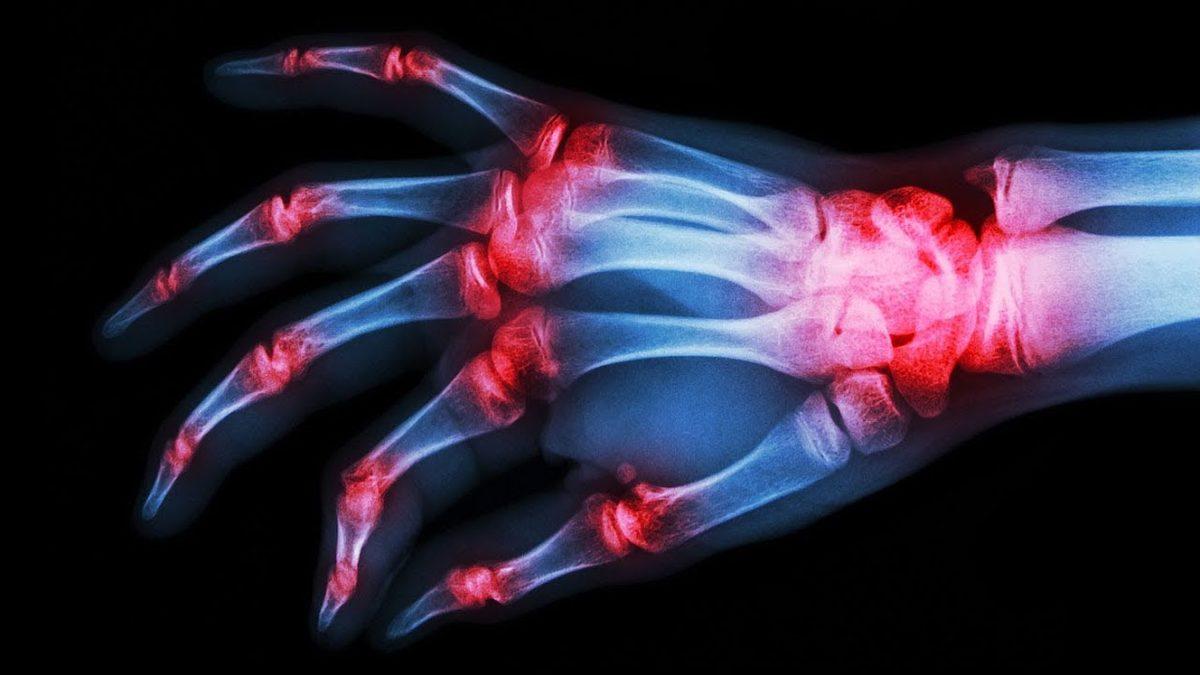

Gut hastalığı tanısı en kolay konulan hastalıklardan bir tanesidir. Atak sırasında röntgen ya da MR çekilmesi ile tespit edilir. Atak anında değilse doktorunuz tarafından istenecek standart bir kan testi sonucuyla da tespit edilebilir. Duruma göre doktor tarafından ürik asit düzenleyici ilaç verilebilir.

Normal kişilerin kanındaki ürik asit seviyesinin üst sınırı 7 mg/dl’dir. Ancak gut hastalarında bu oran 7-9 mg/dl hatta daha yüksek olabilir. Gut hastalığı ürik asidin yüksek olması kaynaklı bir hastalık olsa da tanı konulması için tek etken yüksek ürik asit düzeyi değildir. Kesin bir tanı için atak anında iltihaplı bölgeden sıvı alınıp analiz yapılabilir.